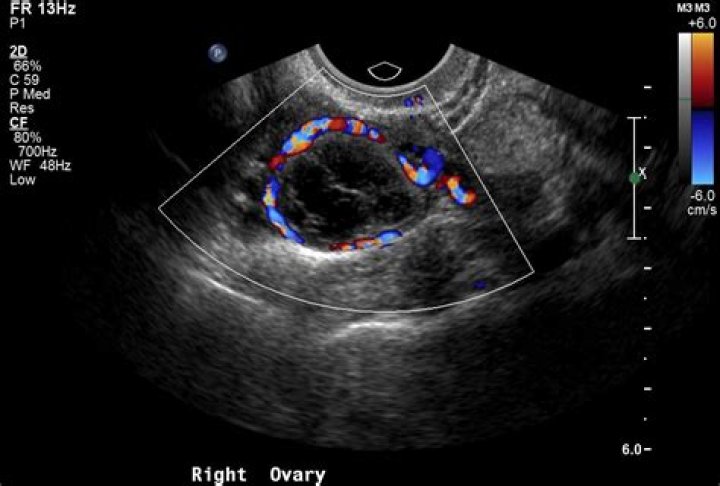

What does red mean on an ultrasound?

By definition, flow towards the transducer is depicted in red while flow away from the transducer is shown in blue. Different shades of red and blue are used to display velocity. Lighter shades of color are assigned to higher velocities.

However, to evaluate the presence and direction of blood flow in the heart and vessels, color Doppler ultrasound has been used. Color Doppler displays blood flow in two basic colors. Red or Red-Orange displays blood flowing towards the top of the screen, and Blue displays flow towards the bottom of the screen.

Vessels in which blood is flowing are colored red for flow in one direction and blue for flow in the other, with a color scale that reflects the speed of the flow. Because different colors are used to designate the direction of blood flow, this Doppler technique simplifies interpretation of the ultrasound data.

Typically, red and blue colors are used to highlight the blood flow in one direction or the other regarding the probe's position. The speed of the blood flow is shown with a color scale. Usually, blood flow away from the probe is shown in blue, while blood flow toward the probe is red.

What do malignant ovarian cysts look like on ultrasound?

The most consistent sonographic signs of malignancy appears to be the presence of papillary excrescences > 3 mm along the internal wall of an ovarian mass and the presence of a solid component21.